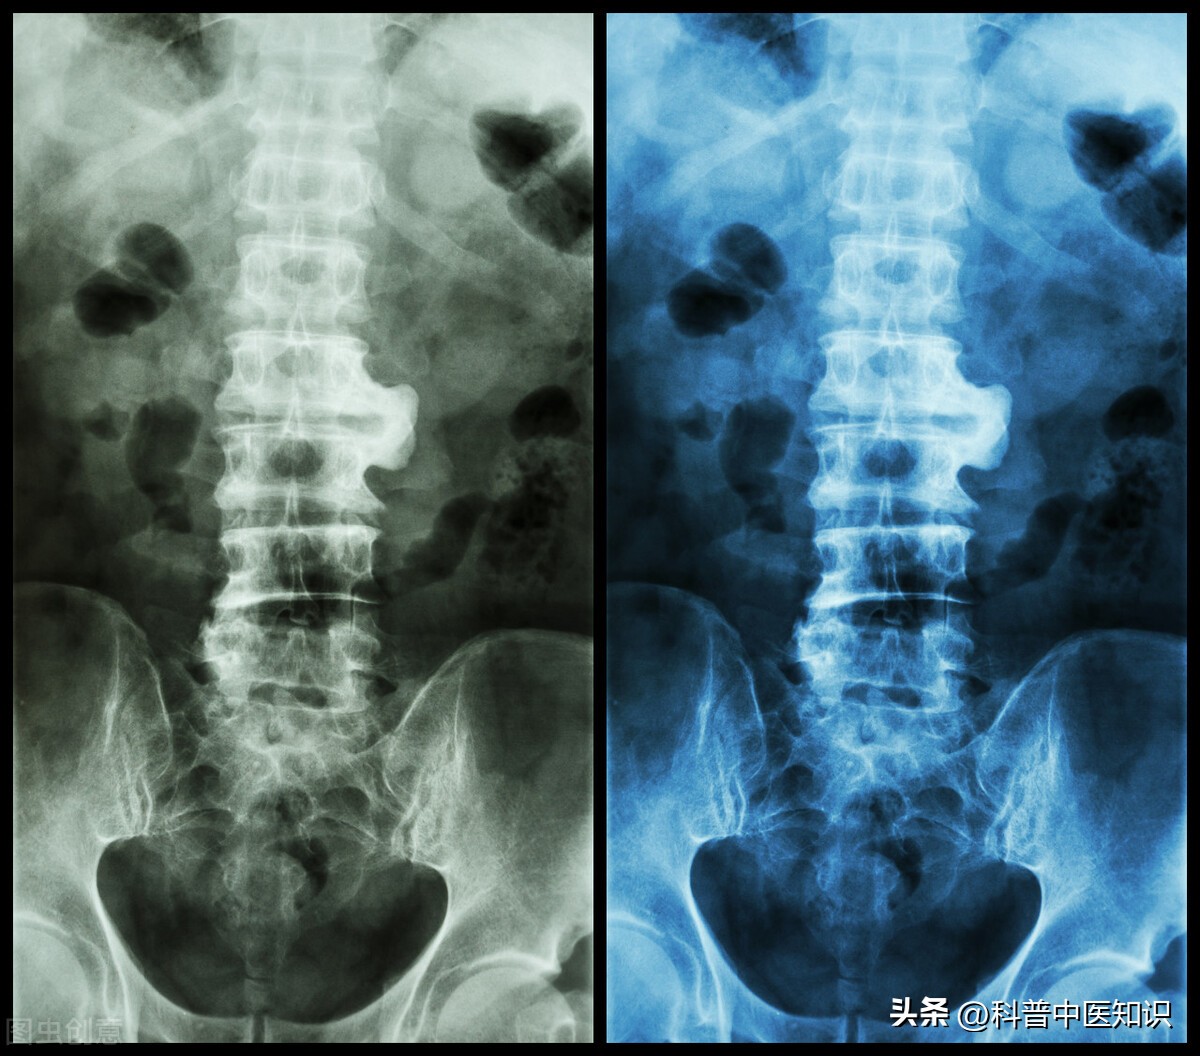

下面是著名中医焦树德教授的一则医案:一男20岁,患者半年前自觉腰髋部及双膝关节疼痛,遇热则痛减,伴僵直不舒。曾于当地医院查血沉70mm/h。予以青霉素、链霉素和炎痛喜康片等治疗无效。近日来腰髋关节痛加重,坐时尤著,腰椎僵直感明显,前弯、侧弯、后仰活动受限,双下肢无力,不能下床活动,生活不能自理。遂收入院治疗。入院后查血沉45mm/h,类风湿因子(-)。腰骶椎正侧位片示:两侧骶髂关节改变符合强直性脊柱炎。查体:腰椎旁压痛(+),腰背肌肉呈板状僵硬,双下肢肌肉萎缩,不能下地行走。舌质淡,舌苔白,脉细滑,诊断为强直性脊柱炎。

强直性脊柱炎过去被认为是类风湿关节炎的一个临床类型。后来发现,HLA-B27阳性的人群易患此病,证明了本病是一个独立的疾病。本病起病迟缓,以持续性腰或涉及胸、颈段脊柱疼痛,晨僵,活动受限,甚则出现驼背、脊柱强直、骶髂关节受损,两腿活动受限等,为主要症状的疾病。强直性脊柱炎的发病男性多于女性,且易多见于15—40岁左右的青少年及中年人。实验室检查90%以上的患者HLA—B27阳性。X线拍片显示:骶髂关节融合。对强直性脊柱炎的治疗,焦树德教授有自己独特的见解。